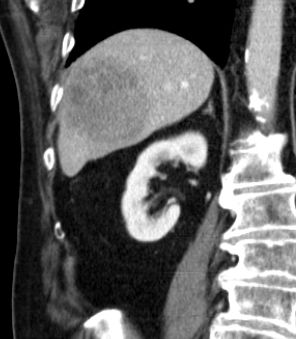

| CT | 60-jähriger Mann mit hepatozellulärem Karzinom in Segment 6.

Histologie: mäßig differenziertes hepatozelluläres Karzinom, G2, Stadium pT1![]() |